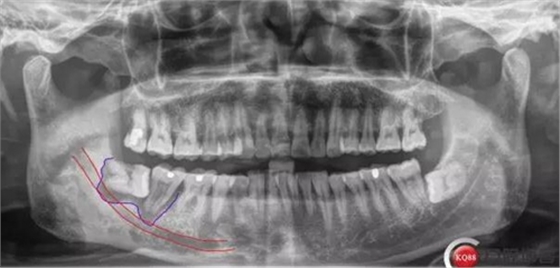

對(duì)于曲面斷層片的分析,當(dāng)智齒埋伏牙的根尖與下牙槽神經(jīng)有重疊影像時(shí),常常可采用觀察重疊部分牙根的牙周膜和硬骨板是否連續(xù),下頜管是否比牙根密度高,下頜管是否變窄等,來(lái)辨別牙根與神經(jīng)管的位置關(guān)系。當(dāng)然曲面斷層片也很難避免其失真變形的自身局限性。拍攝CBCT能更為直觀預(yù)估其風(fēng)險(xiǎn)。但切記盲目的嘗試和挑戰(zhàn)。

X線及CBCT檢查:47、48根尖周區(qū)大面積低密度影像,波及下牙槽神經(jīng)管,部分區(qū)域至神經(jīng)管以下。CBCT顯示神經(jīng)管走形于47根尖炎癥區(qū)下方(已侵犯)48炎癥區(qū)頰側(cè)(已侵犯)